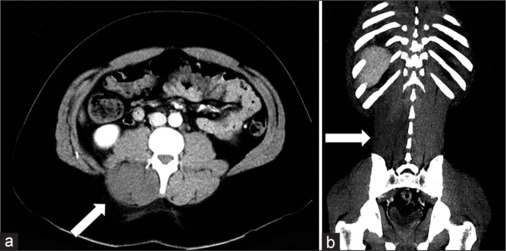

Lumbar paraspinal compartment syndrome is a rare pathology, with only 40 reported cases resulting from an increase in pressure within the muscle compartment. Symptoms typically involve pain and sometimes muscular deficits. The typical patient is a man who has undergone strenuous exercise, with few cases linked to the use of recreational drugs, such as cocaine or ketamine. We report the case of a 25-year-old man presenting to the emergency room with severe diffuse back pain who had recently consumed large amounts of cocaine, ketamine, and alcohol. The patient had diffuse muscular pain, increased serum creatine kinase (CK) levels, and a negative noncontrast abdominal computed tomography (CT), leading to the suspicion of crush syndrome. Over the following days, the patient's pain became more localized to the right paraspinal region, prompting a contrast-enhanced CT. This revealed signs of muscle swelling and edema of the paraspinal muscle, leading to a suspicion of compartment syndrome, which was confirmed by an intramuscular pressure measurement. The patient underwent a surgical fasciotomy. The patient went on to have an unremarkable recovery. Lumbar paraspinal compartment syndrome is exceedingly rare. Cocaine is known to cause rhabdomyolysis both indirectly, due to behavioral disturbances, and directly due to muscle toxicity. Similarly, ketamine use has also been associated with rhabdomyolysis. The rhabdomyolysis results in greatly increased CK levels, sometimes rising up to 100 00 U/L, which should normalize over the following days. A few cases of compartment syndrome, often localized in extremities, have been reported in patients presenting cocaine or ketamine-induced rhabdomyolysis. In this patient, the muscle swelling of the paraspinal muscle resulted in compartment syndrome. Patients who experience cocaine-related rhabdomyolysis have a tendency for nonspecific symptoms, which would match our patient's initial presentation. Although radiology's contribution to the diagnosis is limited, patients suffering from back pain or nonresolving rhabdomyolysis should be submitted to imaging, which may show signs of muscle swelling and edema on CT and magnetic resonance imaging. Diagnosis of compartment syndrome should be confirmed by measurement of muscle pressure, and if elevated, the patient should be proposed for fasciotomy.